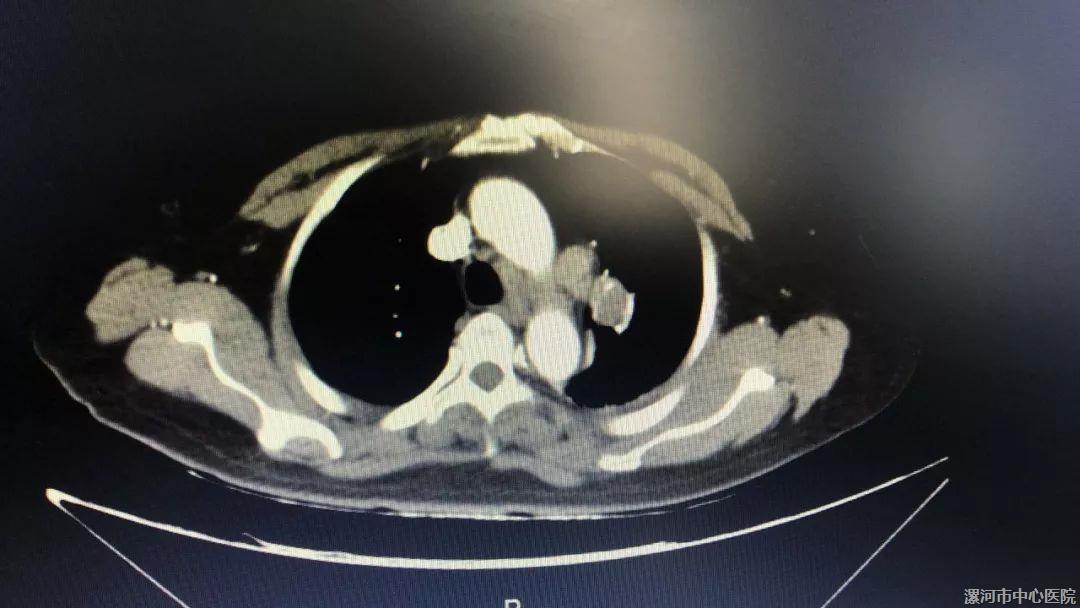

术前CT显示右肺大动脉附近有一肿块

“CT下可见病灶距主动脉弓不足1cm,紧邻大动脉,且由于患者上肢不自主抖动,穿刺难度很高。”胡海英在反复详细测量后选定穿刺部位,经多次定位后,穿刺针终于进入病灶内,但患者此时却出现喉部喘鸣,考虑为穿刺时损伤肺导致出血所致,“以往穿刺时患者如果出现肺部出血,量少时嘱患者慢慢咳出,但此患者神志不清,不能自行咳出。”在各种抢救措施到位、监测氧合良好的情况下,胡海英果断进行了左肺占位的多点穿刺,从病灶内取得足量的组织标本,最终穿刺取得了圆满成功,术后病理为小细胞肺癌,正在免疫组化确诊中。